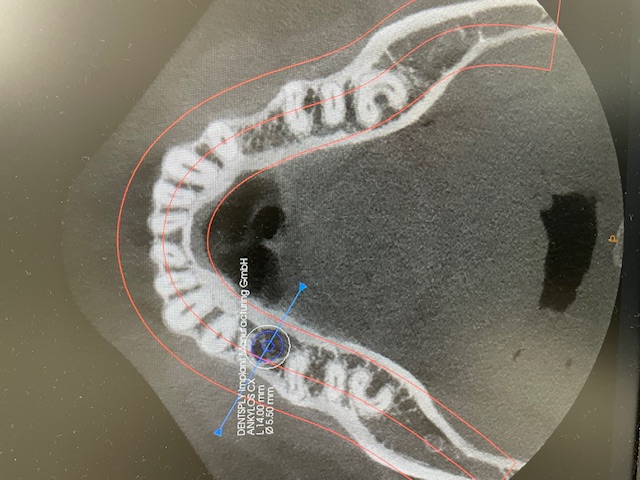

歯科用CT

CT

歯や顎の状態を3次元の立体画像で確認できます。